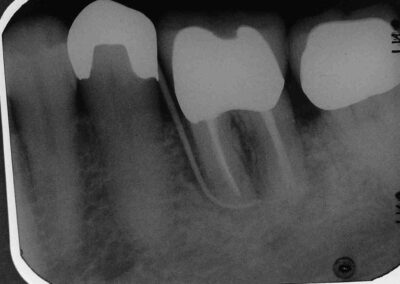

Dieser Patient stellte sich im August 2005 mit einem devitalen 36, leichter druckdolenter Schwellung im Vestibulum und Pus-Austritt aus den Parodontalspalten vor. Der Zahn wies einen Lockerungsgrad von L=0 auf (Klick!).

Auf den ersten Blick ein ganz normaler Paro-Endo-Fall, wie wir ihn mit unserem Endodontie-Protokoll in aller Regel problemlos und voraussagbar erfolgreich konservierend ausheilen.

Anlässlich der Messaufnahme fiel uns zum ersten Mal die wolkige Knochen-Struktur insbesondere im Bereich der distalen Wurzel auf, die bereits in der Ausgangsaufnahme zu erkennen ist, die wir aber vorher nicht beachtet hatten. Anamnestisch gab der Patient an, in diesem Bereich wegen eines tiefen vertikalen Knocheneinbruchs vor geraumer Zeit augmentiert worden zu sein. Der Zahn sei immer vollständig fest und belastbar gewesen und habe bis zu diesem Zeitpunkt nie Beschwerden gemacht.

Der weitere Verlauf war zunächst unauffällig. Die Schwellung ging – wie fast immer – sehr schnell zurück, und die Wurzelkanäle konnten gut zwei Monate später bei vollständiger klinischer Beschwerdefreiheit und Abwesenheit von Exsudat aus den Parodontalspalten abgefüllt werden.

Im Januar 2007 stellte sich der Patient mit Exazerbation und Fistelbildung erneut vor. Wir haben revidiert und unser Desinfektionsprotokoll noch einmal sehr viel geduldiger angewendet. Unter dieser Therapie heilte die Fistel ab und der Patient wurde erneut beschwerdefrei. Diesmal haben wir aufgrund der schlechten Erfahrung jedoch nicht abgefüllt, sondern lediglich die Ca(OH)2-Einlage (Probe-WF) regelmäßig alle 3 Monate erneuert und den Zugang jeweils mit Kunststoff dicht verschlossen.. Bei der klinischen Untersuchung im Mai 2008, also zu dem Zeitpunkt, an dem definitiv abgefüllt werden sollte, war der Patient subjektiv beschwerdefrei. Bei vestibulärem Fingerdruck trat jedoch  wieder reichlich Pus aus dem Parodontalspalt aus, ohne dass bei ausgezeichneter Mundhygiene und L=0 auffällig tiefe Taschen oder gar vertikale Knocheneinbrüche zu sondieren waren.

Da die Kontrollaufnahme eher eine Vergrößerung der Aufhellung zeigt, werden wir den Zahn jetzt extrahieren.